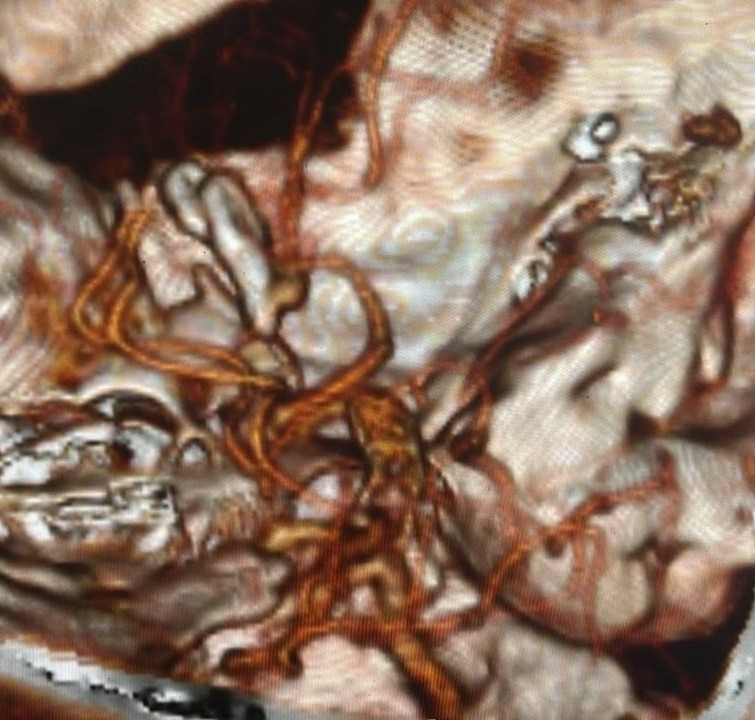

The patient underwent right pterional craniotomy under general anaesthesia. Standard microsurgical dissection along the sylvian fissure was performed. The M1 segment of the MCA was identified and followed distally. The anomalous orbitofrontal branch was identified arising from the superior aspect of the M1 segment. The saccular aneurysm arose from this branching point and measured approximately 7 mm in maximum diameter. The aneurysm neck was carefully dissected free from surrounding arachnoid adhesions and perforating vessels. Two titanium clips were applied across the aneurysm neck, achieving complete obliteration of the aneurysm while preserving the parent orbitofrontal artery and adjacent MCA branches [Figure 4]. Intraoperative indocyanine green (ICG) video angiography confirmed complete aneurysm occlusion with preserved flow in all adjacent vessels. The orbitofrontal artery was successfully preserved. The pterional exposure was adequate to visualize parent vessel anatomy and ensure optimal clip positioning. Hemostasis was achieved, and the craniotomy was closed in standard fashion.

Post-operative NCCT brain and CTA demonstrated complete aneurysm obliteration without residual filling or parent vessel compromise [Figure 5]. The patient was discharged on post-operative day 7 without neurological deficits. Clinical examination remained unremarkable on discharge, with intact higher mental functions. At weekly and subsequent monthly follow-up appointments, he remained neurologically intact without recurrent symptoms, vasospasm related complications and there was no evidence of delayed cerebral ischemia, hydrocephalus, or clip migration. Neuropsychological assessment revealed no cognitive deficits or frontal lobe dysfunction. Higher mental functions remained completely intact. At three-month follow-up, the patient had resumed occupational activities without restrictions.